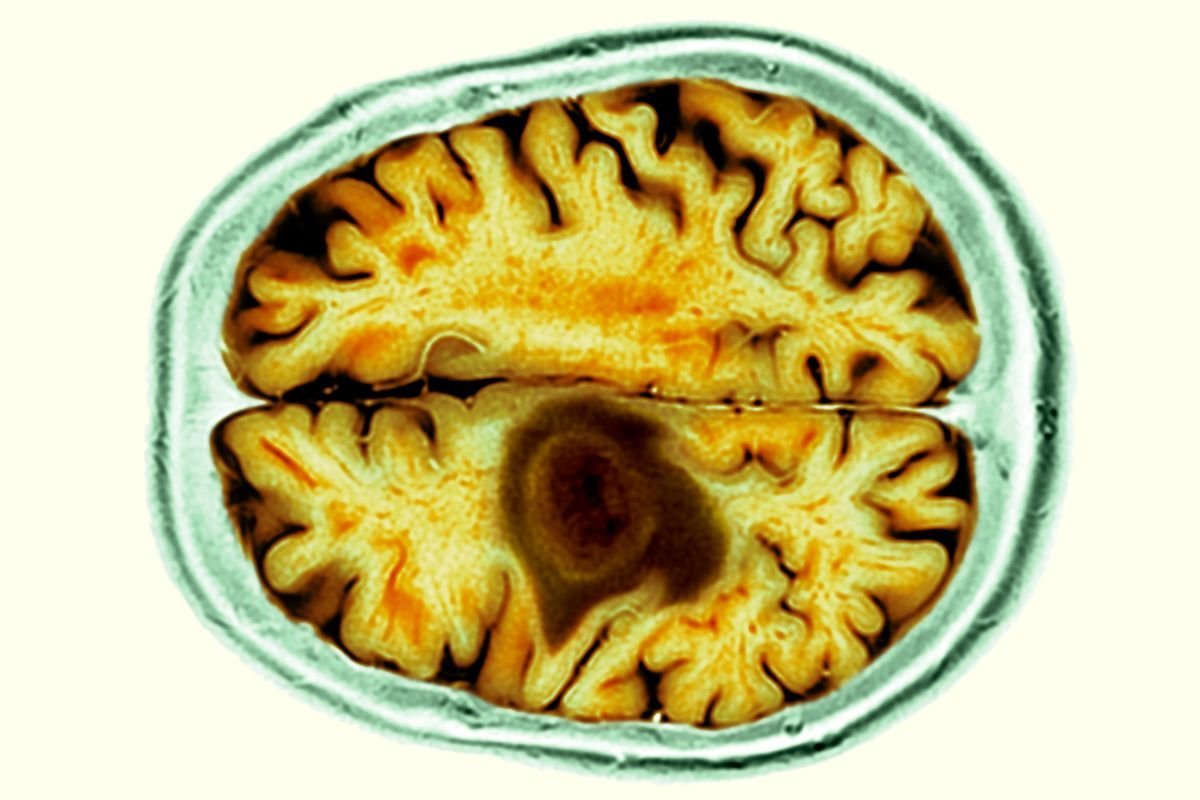

Almost 50% of new colon cancer cases now hit younger adults – scientists warn of potential causes

Almost half of new colon cancer cases now affect adults under 65, according to a recent study